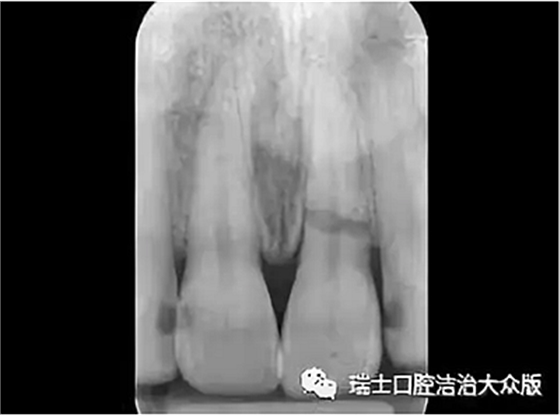

2、根折(圖5)

成人牙齒外傷了怎么應急處理?

圖5.根折

即牙根的折斷,癥狀表現(xiàn)為牙齒松動或移位,咬合不適或叩診疼痛,可伴有牙齦出血。此時應避免進食,防止牙齒的進一步移位,及時就診,醫(yī)生檢查后進行相應處理。